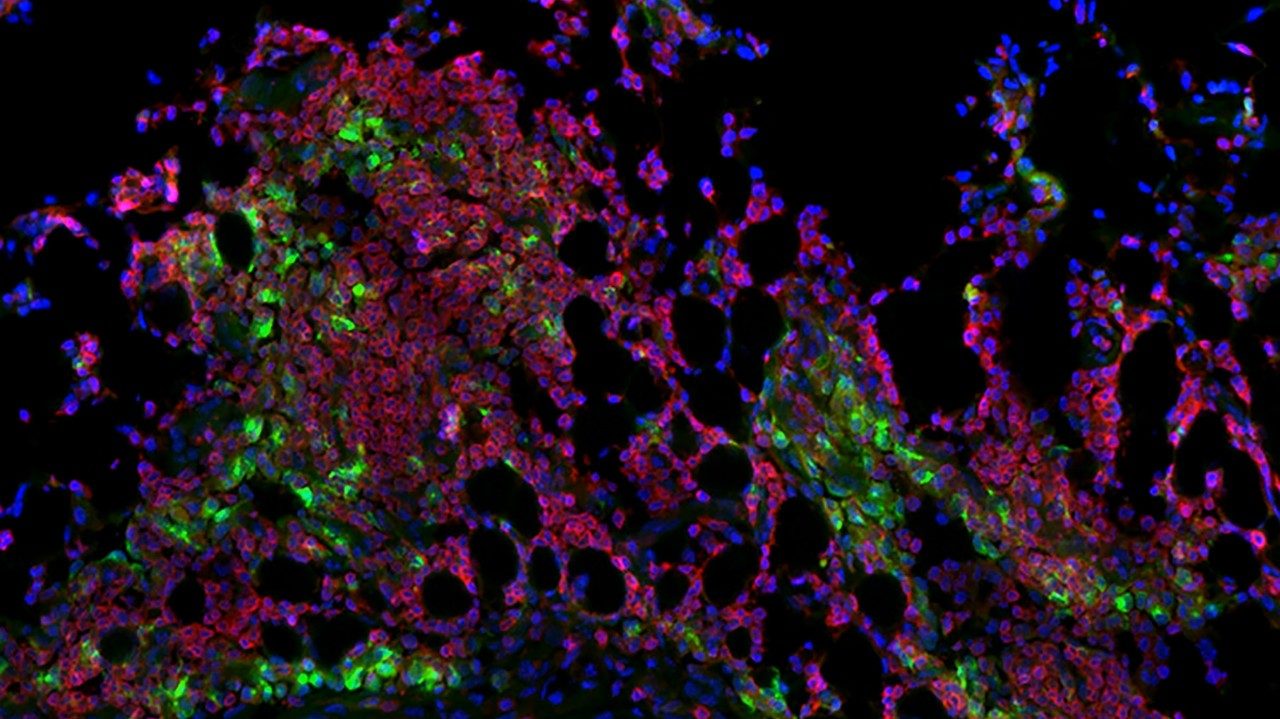

3. Bispecific T-cell engagers for patients with central nervous system multiple myeloma

Mahmoud Gaballa, M.D., assistant professor of Lymphoma and Myeloma, will also present a study on bispecific T-cell engagers, only this research looked at patients who have multiple myeloma with central nervous system involvement. These patients tend to have a poor prognosis, so better treatments are needed.

In a retrospective study, Gaballa and his team looked at patients treated with teclistamab, talquetamab or elranatamab at 13 different institutions. All of the patients in the study had at least three prior rounds of treatment, including prior transplant and prior CAR T cell therapy. The researchers found that bispecific T-cell engagers are safe, with no increased risk of immune effector cell-associated neurotoxicity syndrome, which is a side effect of T cell engaging immunotherapies.

The study also found that one patient treated with bispecific T-cell engagers as a bridging therapy to CAR T had the longest progression-free survival. Therefore, future research to evaluate this combination’s efficacy in this very high-risk population may be warranted.